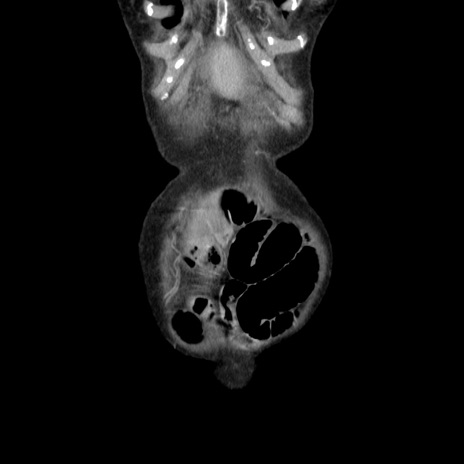

症例25(冠状断像)

横断像